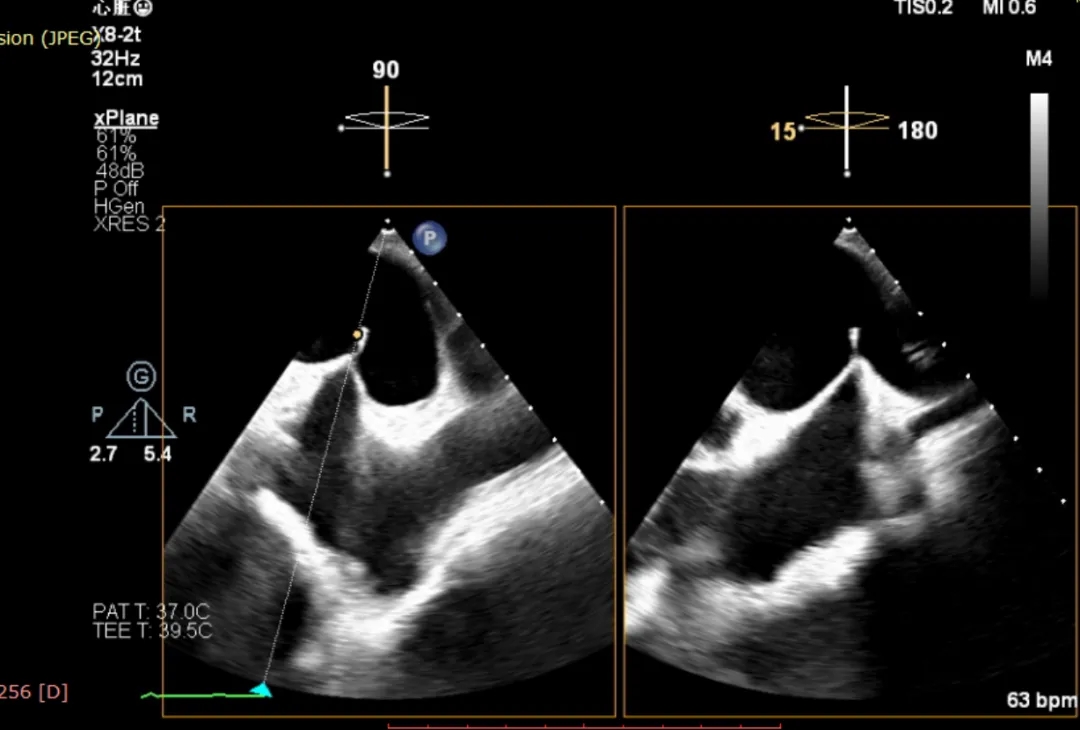

重度反流

3D enface进行Orientation调整

捕捞并夹持瓣叶

反流降低

组织桥稳定

术后平均跨瓣压差3mmHg